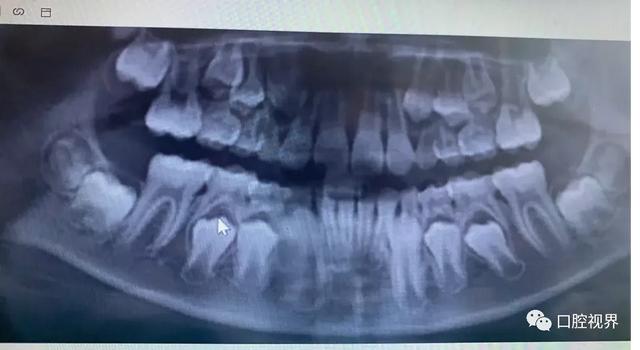

第二种是以检查全口牙齿的整体情况为目的的全景片。

全景片可以拍摄到所有牙齿的形态,位置以及颌骨内的情况。特别是儿童,可以观察到乳恒牙发育的整体状况,了解牙齿数目,牙间关系和牙齿替换的情况,同时乳牙牙根吸收情况,恒牙萌出方向以及上下颌骨的情况。

如图所示,数一数有44颗牙齿,每个牙齿的发育阶段都不一样,有正在钙化的牙齿,有牙根还未发育完全的牙齿,有牙根已经形成的牙齿,等等。

有了牙片,医生可以很好地从图片上看出问题,有牙齿该掉的时候不掉,该长的时候不长,乳牙滞留了,需要尽快拔除。

另外图片上还能够看出是否有多生牙,以及多生牙的位置是否会阻挡换牙,特别是需要拔智齿的朋友,医生都会建议拍牙片,才知道智齿牙根的数量位置,制定相对应的拔除方案。